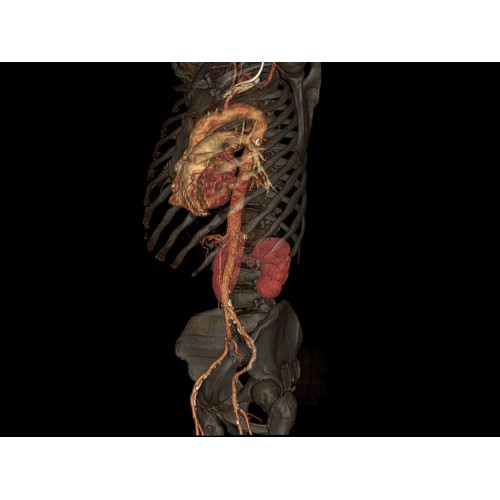

Кардиология

• Неинвазивная оценка состояния коронарных артерий.

• Диагностика атеросклероза и других сердечно-сосудистых патологий.